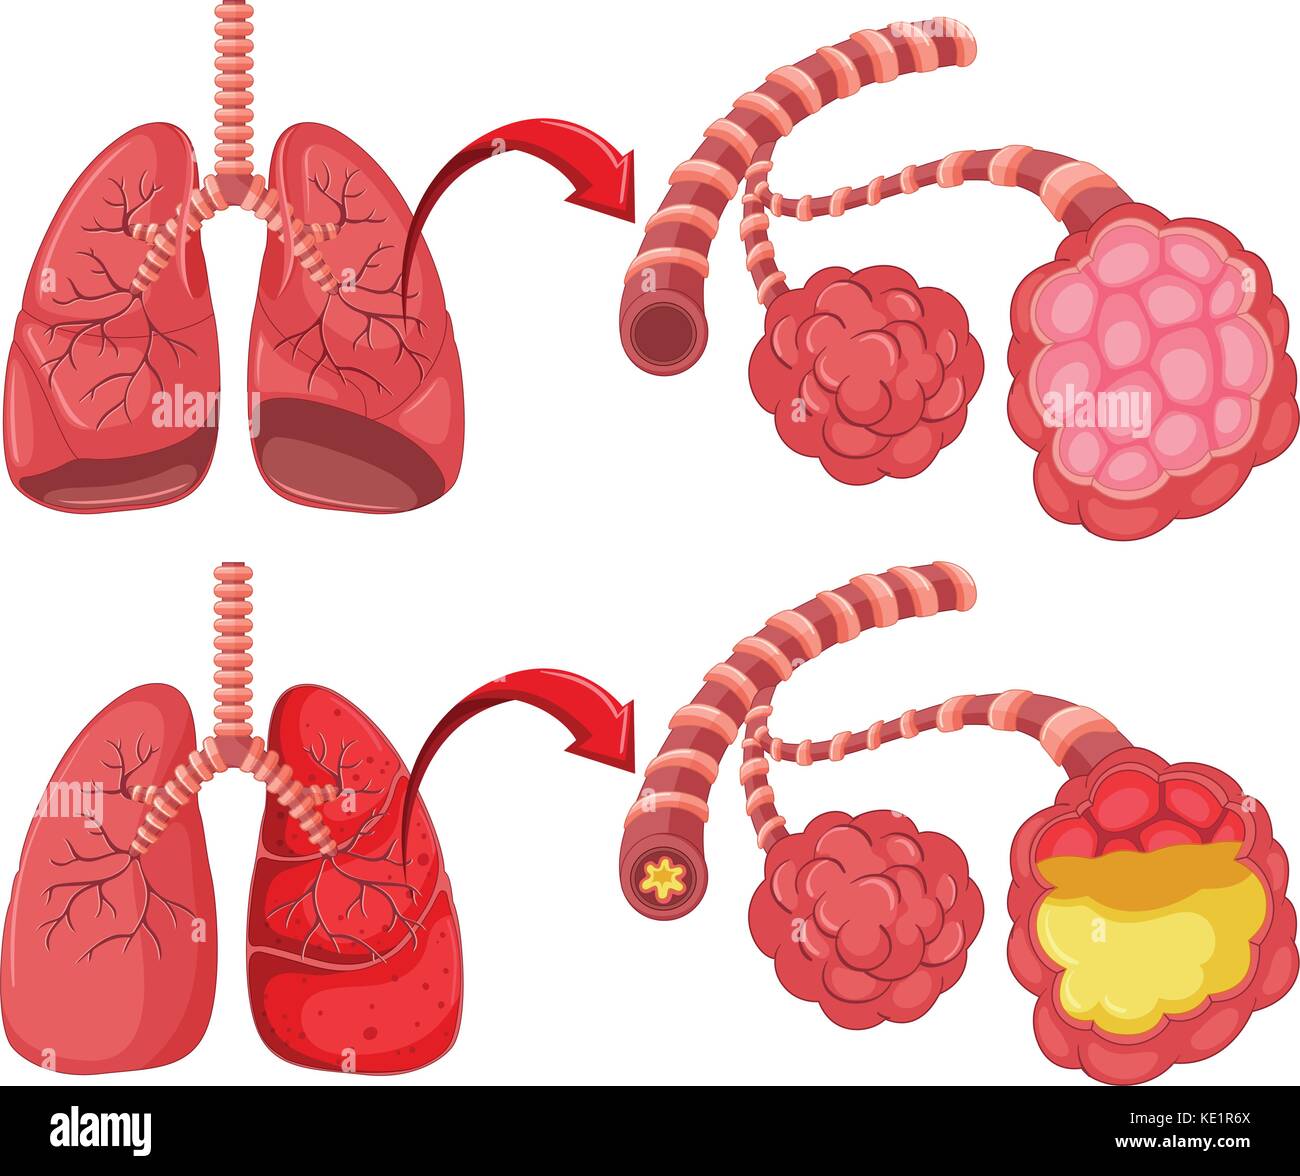

Lista es una colección y muestra de imágenes sobre imagenes de pulmones sanos y enfermos realizada por upup.edu.vn. Además, hay imágenes relacionadas con imagenes de pulmones sanos, imágenes de pulmones sanos, radiografía de pulmones sanos y enfermos, fotos de pulmones sanos, radiografía pulmones sanos y enfermos, rayos x de pulmones sanos y enfermos, pulmon sano y enfermo, pulmón sano y enfermo . Para más información, consulta a continuación.

imagenes de pulmones sanos y enfermos

Posts: imagenes de pulmones sanos y enfermos